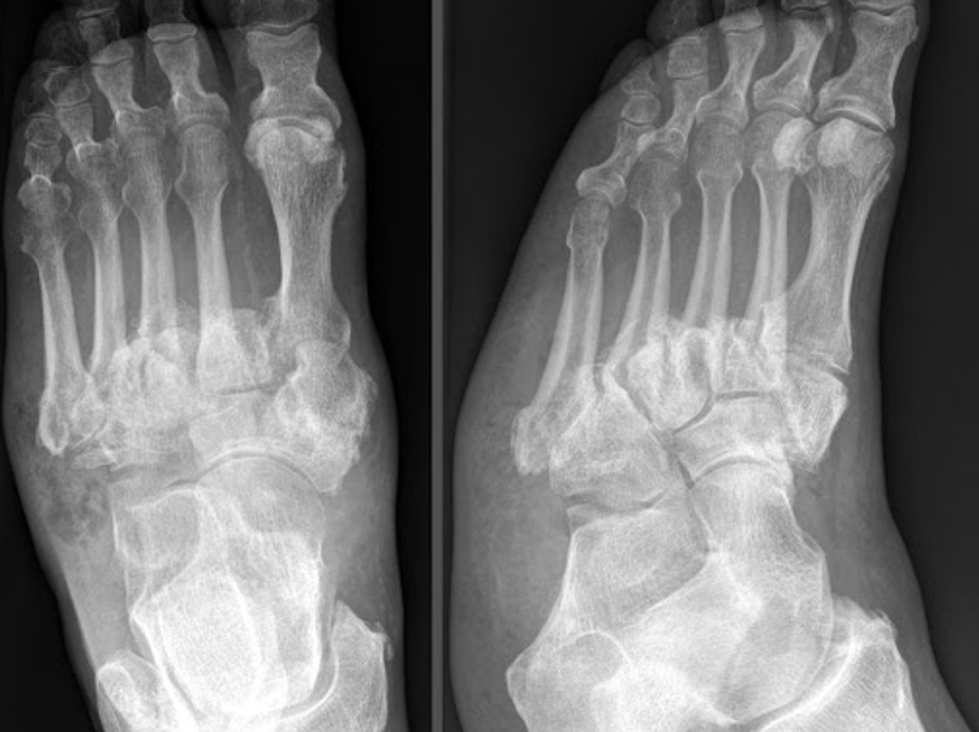

Bệnh khớp do thần kinh (hay còn gọi là bệnh Charcot) là những thay đổi về xương và khớp xảy ra thứ phát do mất cảm giác và thường liên quan nhất đến bệnh đái tháo đường, giang mai, sa xương sống, nứt đốt sống, chấn thương tủy sống và bệnh phong. Những thay đổi trên X quang của bệnh lý này bao gồm phá hủy bề mặt khớp, xương dưới sụn mờ đục, mảnh vỡ khớp, biến dạng và trật khớp.

Tiến hành chẩn đoán bệnh khớp do thần kinh cho bệnh nhân mắc chứng rối loạn thần kinh có khuynh hướng phát triển một bệnh khớp có tính chất hủy hoại nhưng không gây cơn đau bất ngờ, thường kéo dài vài năm sau khi khởi phát tình trạng bệnh lý thần kinh cơ bản. Nếu nghi ngờ bệnh khớp do nguyên nhân thần kinh, nên chụp X quang. Chẩn đoán được xác định bằng những bất thường đặc trưng trên hình ảnh X quang cho bệnh nhân có nguy cơ cao hoặc có các triệu chứng và dấu hiệu điển hình.

Những bất thường trên X quang trong bệnh khớp do thần kinh thường tương tự như trong bệnh viêm xương khớp (Osteoarthritis – OA). Các dấu hiệu chính bao gồm:

- Sự phân mảnh xương;

- Hủy xương;

- Phát triển xương mới;

- Mất khe giữa các khớp.

Cũng có thể thấy cấu trúc khớp lỏng lẻo và tràn dịch khớp. Sau đó, xương bị biến dạng và hình thành xương mới liền kề với khớp, bắt đầu trong bao khớp và thường kéo dài lên trục, đặc biệt là ở các xương dài. Hiếm khi xảy ra quá trình vôi hóa và hóa lỏng trong các mô mềm. Các tế bào xương lớn, có hình dạng kỳ lạ có thể có ở rìa khớp hoặc trong khớp. Các tế bào xương cong lớn (mỏ vẹt) thường phát triển ở cột sống nếu không có bệnh lý cột sống lâm sàng.

Trong giai đoạn đầu, bệnh khớp thần kinh có thể tương tự viêm khớp. Tuy nhiên, bệnh khớp thần kinh tiến triển nhanh hơn bệnh viêm khớp và thường ít gây đau hơn.

Chẩn đoán xác định

Dựa vào tiền sử mắc phải các bệnh lý gây tổn thương thần kinh (như giang mai, phong, đái tháo đường, bệnh rỗng tủy…) gây đau, sưng khớp với tiến triển tồi tệ dần theo thời gian, bất cân xứng giữa mức độ đau với mức độ tổn thương khớp và kết hợp với chụp X quang để khẳng định chẩn đoán.